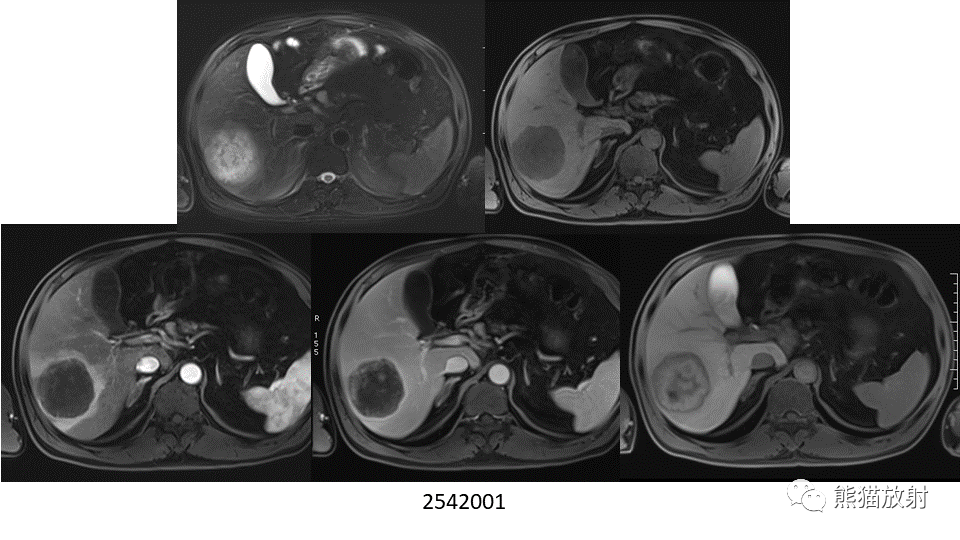

【PPT】肝内胆管细胞癌 VS 肝脓肿

【PPT】肝内胆管细胞癌 VS 肝脓肿-2